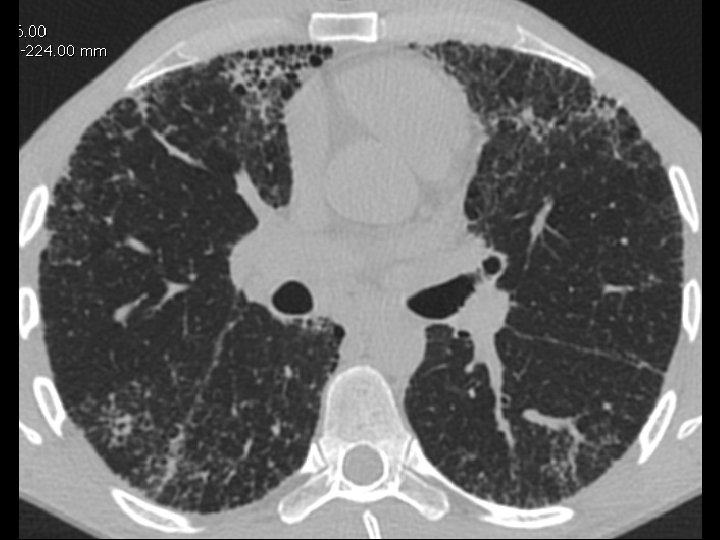

High-resolution CT scan

Subpleural, basal predominance Reticular abnormality Honeycombing with traction bronchiectasis UIPUIP Pattern

Subpleural, basal predominance Reticular abnormality Honeycombing with traction bronchiectasis Profuse micronodules UIPUIP Pattern Inconsistent with UIP Pattern

39 yo caucasian male, works in car collision repair and painting Multiple allergies, Gastroesophageal reflux disease and Thrombocytopenia of unknown etiology Smoker. No drugs CT: Reticular abnormality and honeycombing of subpleural basal predominance + micronodules Lung function tests: decreased diffusion capacity of the lung Blood tests: small increase of ESR and CRP; Autoimmune screening blood tests were normal BAL: normal celularity, with a mild increase in the neutrophil and eosinophil count

39 yo caucasian male, works in car collision repair and painting Multiple allergies, Gastroesophageal reflux disease and Thrombocytopenia of unknown etiology Smoker. No drugs CT: Reticular abnormality and honeycombing of subpleural basal predominance + micronodules Lung function tests: decreased diffusion capacity of the lung Blood tests: small increase of ESR and CRP; Autoimmune Screening Blood Tests were normal BAL: normal celularity, with a mild increase in the neutrophil and eosinophil count Definitive diagnosis can be established? Additional diagnostic tests required? Which tests?